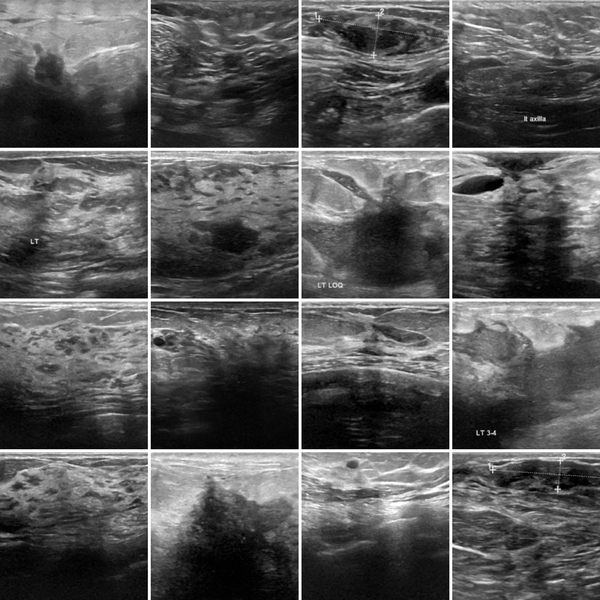

Breast 2D 546/78/156 2 Ultrasound

Figure 1: Overview of the 12 selected datasets from the MedMNIST V2 collection used in this study. Each sub-figure shows some representative example images along with the dataset name, imaging modality, and classification task. For the 3D datasets, the middle slices from random samples are shown.